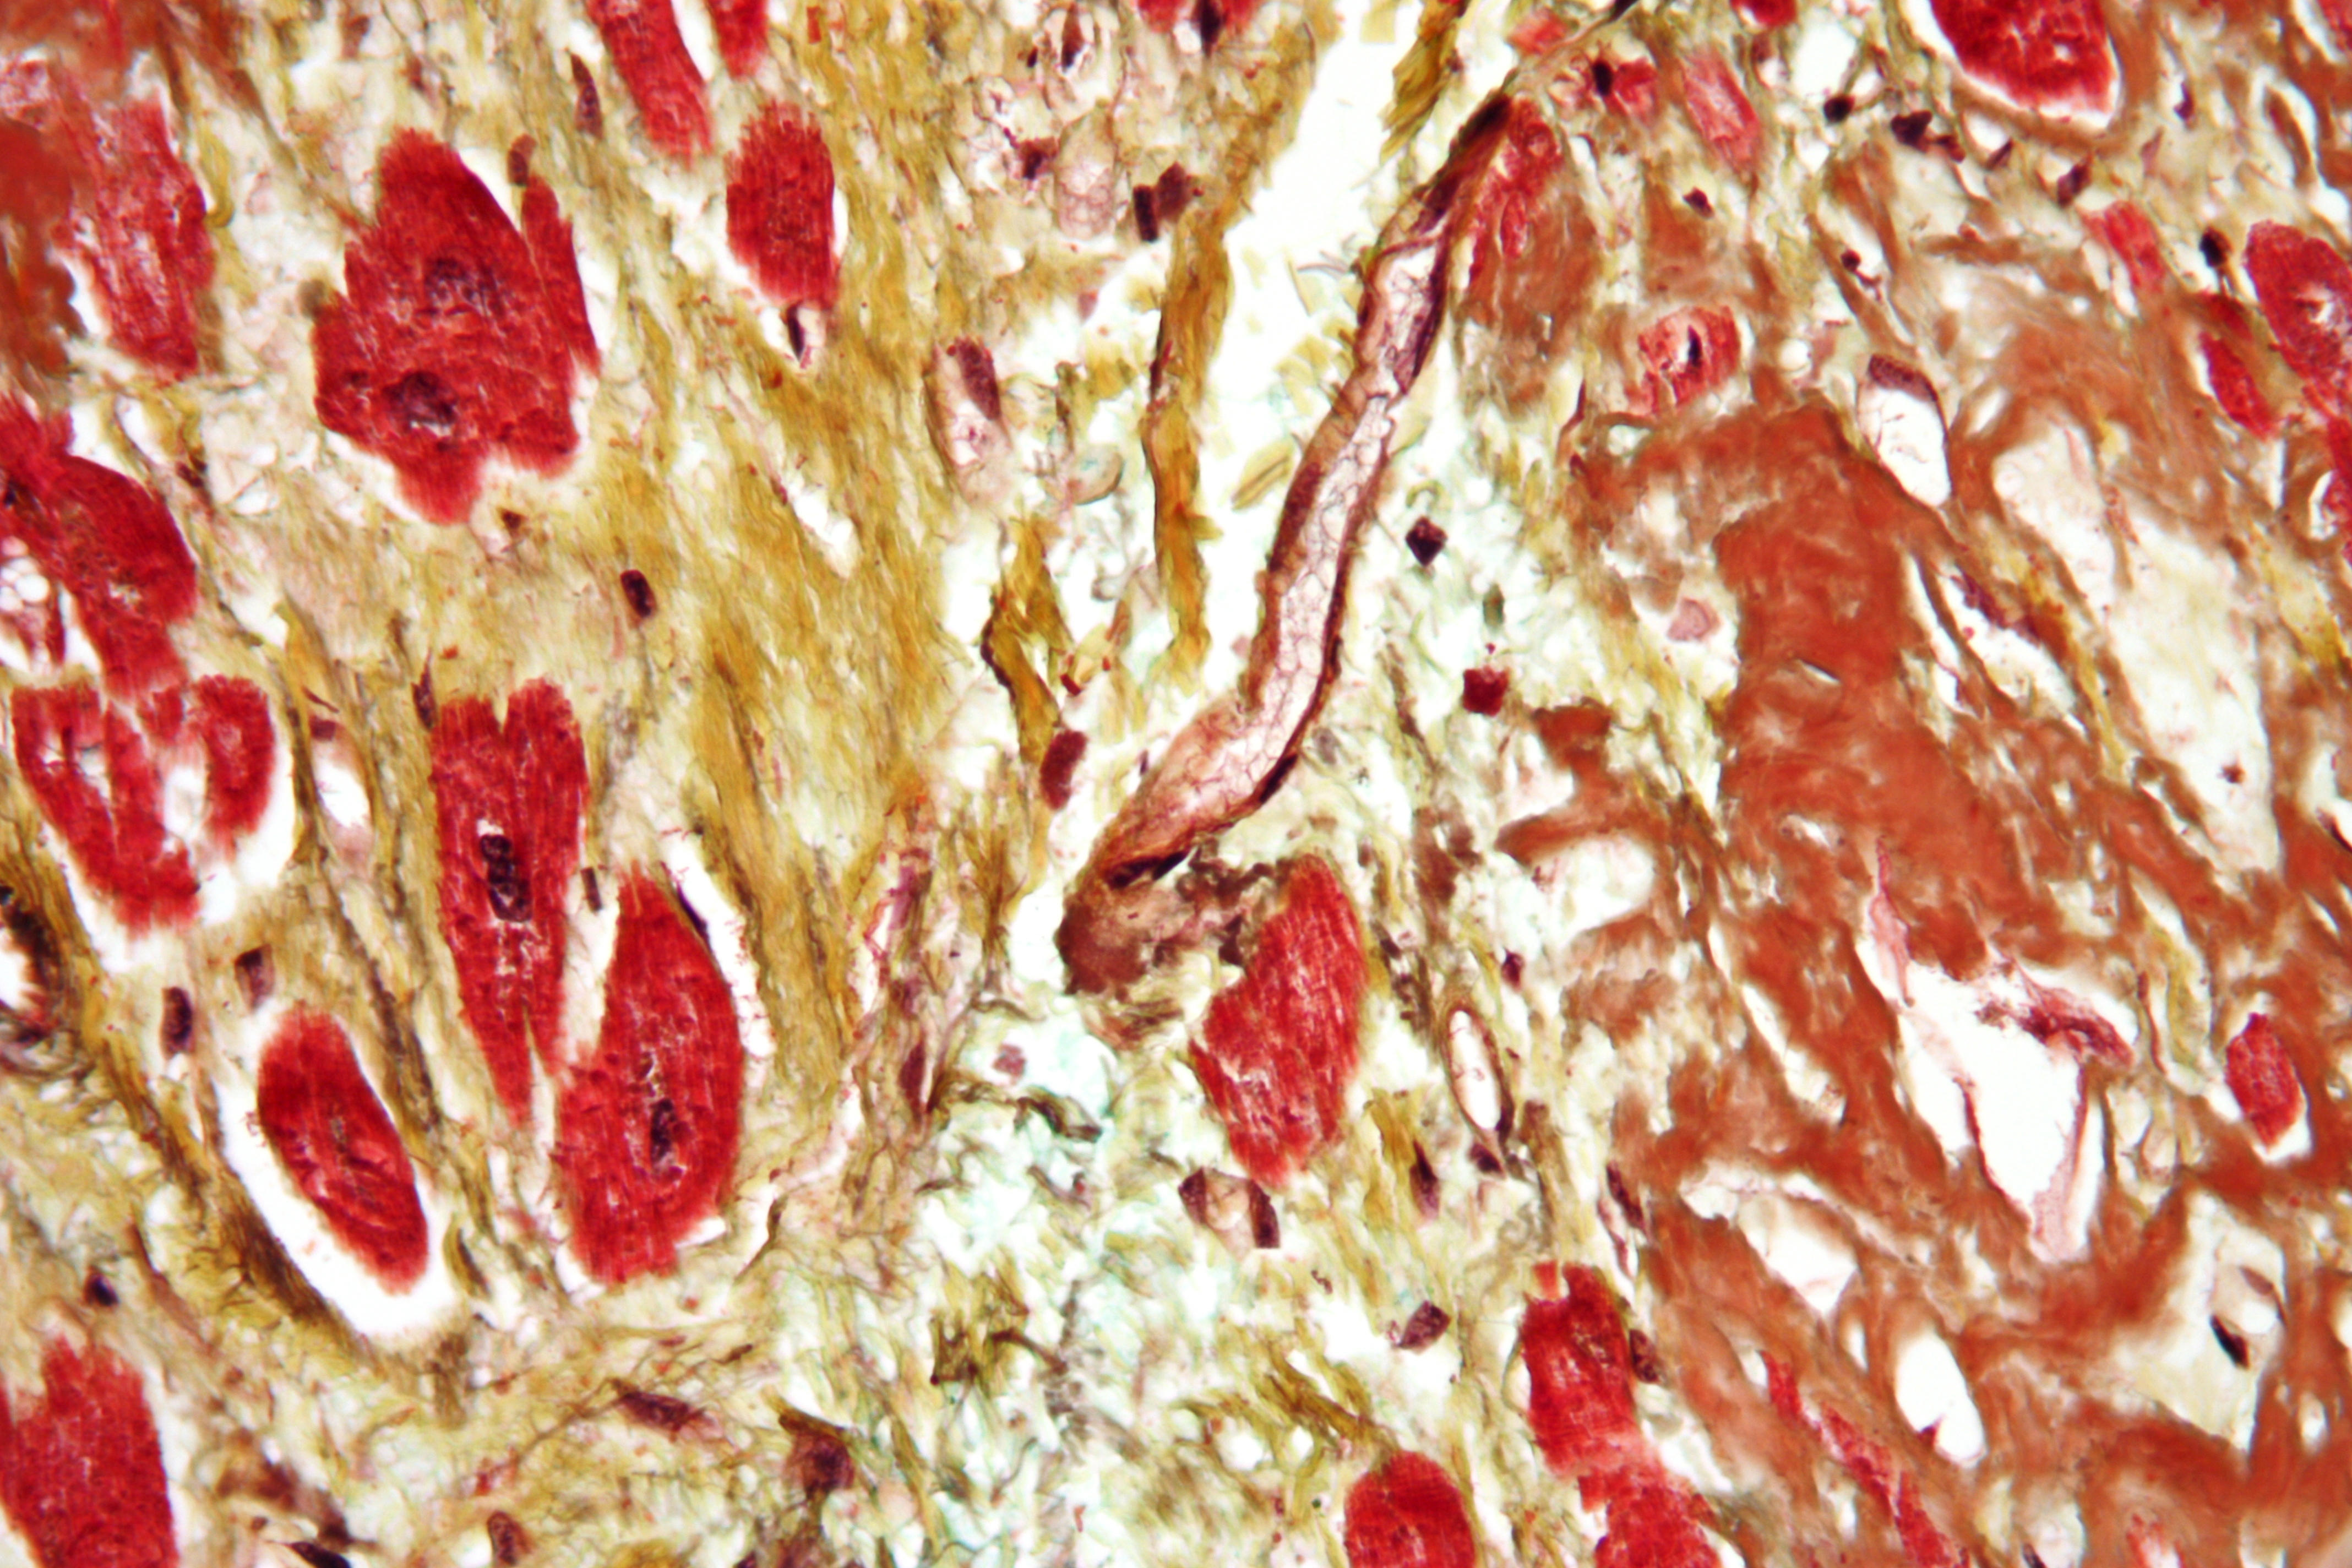

심장혈관 질환 - 동맥경화증 동맥경화증은 동맥 벽이 굳고 두꺼워지는 질환으로, 세동맥경화증, 묀케베르크 경화증, 죽상동맥경화증으로 나뉘며, 특히 죽상동맥경화증은 혈관 내 죽상판 형성으로 심혈관 질환을 유발하는 주요 질환이다.

죽상동맥경화증은 심혈관 질환의 주요 원인으로, 혈관 내벽에 콜레스테롤 등이 쌓여 혈관이 좁아지고 딱딱해지는 현상이다. 인구 기반 연구에 따르면, 이러한 죽상동맥경화증은 어린 시절부터 시작될 수 있다. 청소년의 죽상동맥경화증 병리 생물학적 결정 인자(PDAY) 연구에서는 7~9세 청소년의 대동맥과 오른쪽 관상 동맥의 절반 이상에서 내막 병변이 나타난다는 것을 보여준다.[214][79]